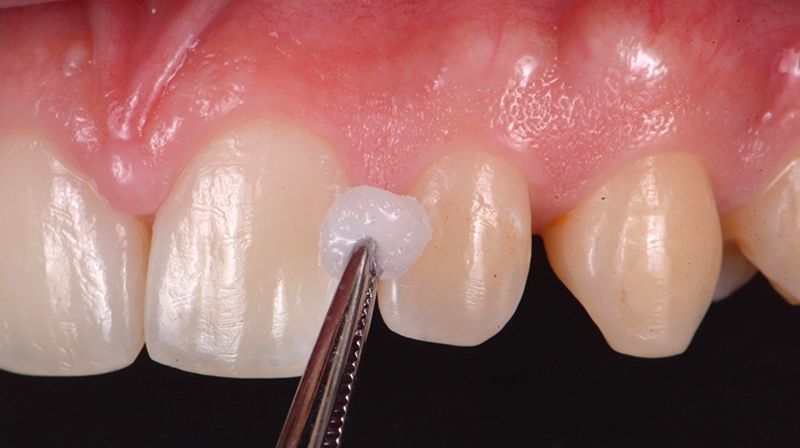

Per applicare il prodotto sulla lesione, isolare l’elemento da trattare con dei semplici rulli di cotone (non è richiesto l’utilizzo della diga di gomma) e distribuire il prodotto uniformemente sulla lesione, premendo bene la spugnetta in modo da far uscire il liquido, anche esercitando una pressione sull’applicatore mediante uno strumento quale una spatola di Heideman (Fig. 3). Grazie alla sua capacità di penetrare nelle microporosità e alla sua elevata affinità per l’idrossiapatite, il peptide riesce a raggiungere i siti danneggiati all'interno dello smalto demineralizzato fino alla profondità della lesione. Così, nel caso di lesioni cariose iniziali prossimali, è sufficiente premere la spugna dal lato buccale e linguale della zona prossimale. Poi, lasciare agire per circa 5 minuti la soluzione, al fine di permettere al peptide di auto-assemblarsi e formare la matrice peptidica che guiderà la remineralizzazione. Al termine del periodo di posa, il paziente può essere dimesso con la raccomandazione di non bere e non mangiare per circa 30 minuti.

Fig. 3 - Applicazione di CURODONT™ REPAIR (Da: G. Sammarco. Cariologia Clinica. Quintessence publishing Italia, 2025).